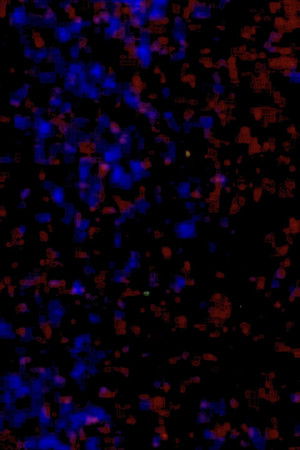

The only remaining segment from an unfinished project by Henry Crawford.